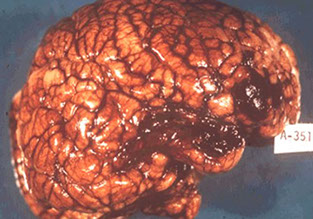

Herpes simplex encephalitis

MCC sporadic encephalitis in the USA; results in severe acute

necrotizing encephalitis, asymetrically involving the temporal lobes with extension to frontal lobes; can be hemorrhagic

- Cowdry type A intranuclear inclusions are identified in neurons

and glial cells. Virus can also be specifically identified by IHC c antibody to Herpes simplex.